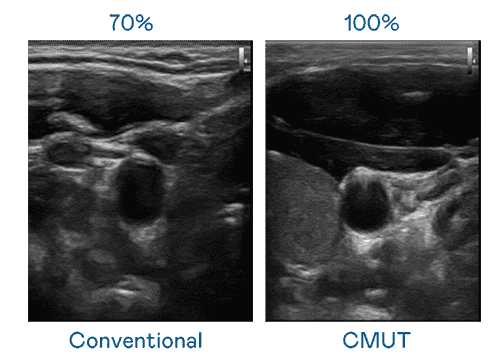

CMUT 技术是一种用电容式微机电元件来产生超音波讯号的技术。。。与传统 PZT 压电式技术相比,,,CMUT 频宽增加 30%,,更宽频的超音波讯号让影像解析度大幅提升,,,,是实现高影像品质医疗超音波扫描、、、、促进精准医疗发展的关键技术。。

大频宽带来超清晰影像

超音波影像的解析度高低,,首先取决于探头能发出的讯号频宽。。。开云电子 CMUT 可提供高清晰的超音波讯号,,,,提供高频宽、、高灵敏度、、、影像纹理细节更高的超音波影像,,,协助医护人员缩短影像判读时间及利用精准的医疗影像进行诊断。。。